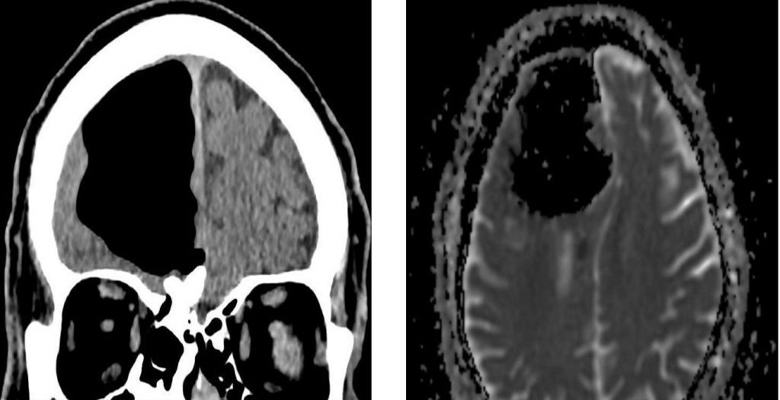

Zdravniki iz Severne Irske so bili ob pregledu presenečeni pred kratkim 84-letni bolnik, ki je k njim prišel z slabo počutjem. Po opravljenem slikanju z magnetno resonanco glave moškega zdravniki nepričakovano odkril, da mu manjka del desnega čelnega dela režnja možganov. Namesto tega je bila v lobanji upokojenca zrak žep. Potem so zdravniki ugotovili, da je dejanski fragment možganov pacient ni nikjer izginil, ampak se je mešal v smeri tega nenormalnega votlina.

Osebje bolnišnice je predlagalo, da bolnik vodi težko operacijo odstranitve zračnega žepa, vendar je moški to zavrnil od operacije. Po njegovem mnenju upokojenec za svojega starost, ponavadi se počuti zelo dobro in ne namerava svoje življenje ogrožati tako, da leži pod skalpelom. Do na srečo je kmalu dobro počutje Irca izginilo in v sedanjosti trenutek, ko ne občuti nobenega nelagodja, povezanega z njihovo nenormalno zdravstveno stanje.